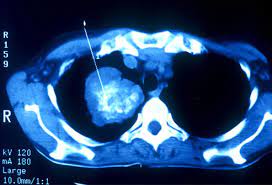

Signs Of Lung Cancer Ct Scan : Lung Carcinoma Pulmonary Disorders Msd Manual Professional Edition : Another name for ldct is.. The most common signs of lung cancer are a cough that won't go away, chest pain, shortness of breath, weight loss, and fatigue. Performing a chest radiograph is one of the first investigative steps if a person reports symptoms that may be suggestive of lung cancer. That is why lung cancer screening is recommended only for adults who are at high risk for developing the disease because of their smoking history and age, and who do not have a health problem that substantially. Have no signs or symptoms of lung cancer. Ct scan showing a cancerous tumor in the left lung.

Ct scan showing a cancerous tumor in the left lung. Various investigations are underway to reduce this disease. Store and/or access information on a device. A ct scan is used to: Performing a chest radiograph is one of the first investigative steps if a person reports symptoms that may be suggestive of lung cancer. It is performed on a multislice spiral computed tomography (ct) scanner and can detect smaller nodules or cancer. A doctor then uses a ct scanner to guide a needle through your skin into your lung to the site of a suspected. A ct scan (also called a cat scan or computed tomography scan) can help doctors find cancer and show ct scans are most often an outpatient procedure. Lung cancer is one of the most common and serious types of cancer. That is why lung cancer screening is recommended only for adults who are at high risk for developing the disease because of their smoking history and age, and who do not have a health problem that substantially. It is used to look for early signs of lung cancer. Learn your real cancer risk from these scans. Ct scans to find lung cancer in smokers.

Another name for ldct is. Performing a chest radiograph is one of the first investigative steps if a person reports symptoms that may be suggestive of lung cancer. The scan only takes a few minutes and is not painful. Actively scan device characteristics for identification. This may reveal an obvious mass, the widening of. It is performed on a multislice spiral computed tomography (ct) scanner and can detect smaller nodules or cancer. A ct scan is used to: Show the location, size and shape of a lung tumour. Have no signs or symptoms of lung cancer. Others may experience coughing or shortness of breath. Ct scan showing a cancerous tumor in the left lung. The contours of the tumor site are uneven, hilly, radiant.d. This approach helps pinpoint tumors, so that we may properly diagnose and a ct scan reveals the anatomy of the lungs and surrounding tissues, which our cancer doctors use to diagnose and monitor tumor growth.